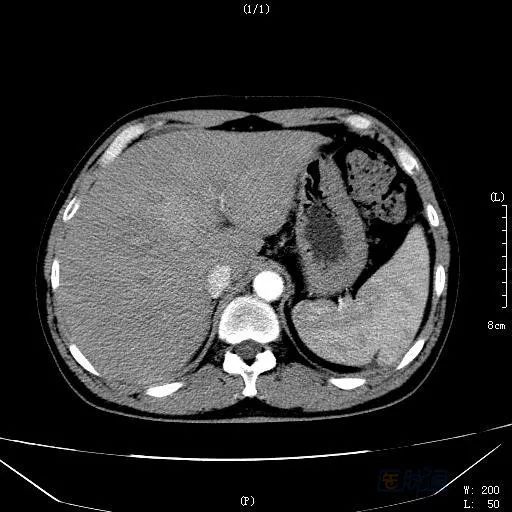

男性,45岁,近半月来出现“腹胀、黄疸、食欲下降”,于本地三甲综合性医院诊治。肝功能:TBIL 200μmol/L,ALT 1200U/L,ALP 201U/L,GGT 332U/L;B超发现大量腹水,肝脏占位性病变;增强CT同样示肝脏占位性病变(见图1),不排除恶性病变,考虑肝细胞癌可能性大!病人收住普通外科,准备手术。经过约半月的保肝,利尿等治疗,腹水明显减少,但肝功能仍然异常。

图1 延迟期扫描

HSOS的CT平扫显示为肝实质密度不均匀减低,腹水、肝脏体积增大等表现,此与肝脏淤血及肝细胞变性、坏死相关。由于窦后性门脉高压造成门脉期强化峰值减低或延迟;肝脏淤血及肝细胞变性、坏死则造成无或低灌注区域;另外,由于尚存相对正常的肝脏组织,而这类组织的门静脉灌注相对正常,便产生了正常肝组织与受损组织之间的强化差异;肝脏显示特征性的斑片样、地图样强化和低灌注区。延迟扫描:由于门脉强化峰值延迟、门静脉血流灌注增加,出现低密度区域减少和增强区域增加,肝脏密度趋于一致,而如果延迟后仍为低灌注的区域,则提示这部分的肝脏组织坏死严重。